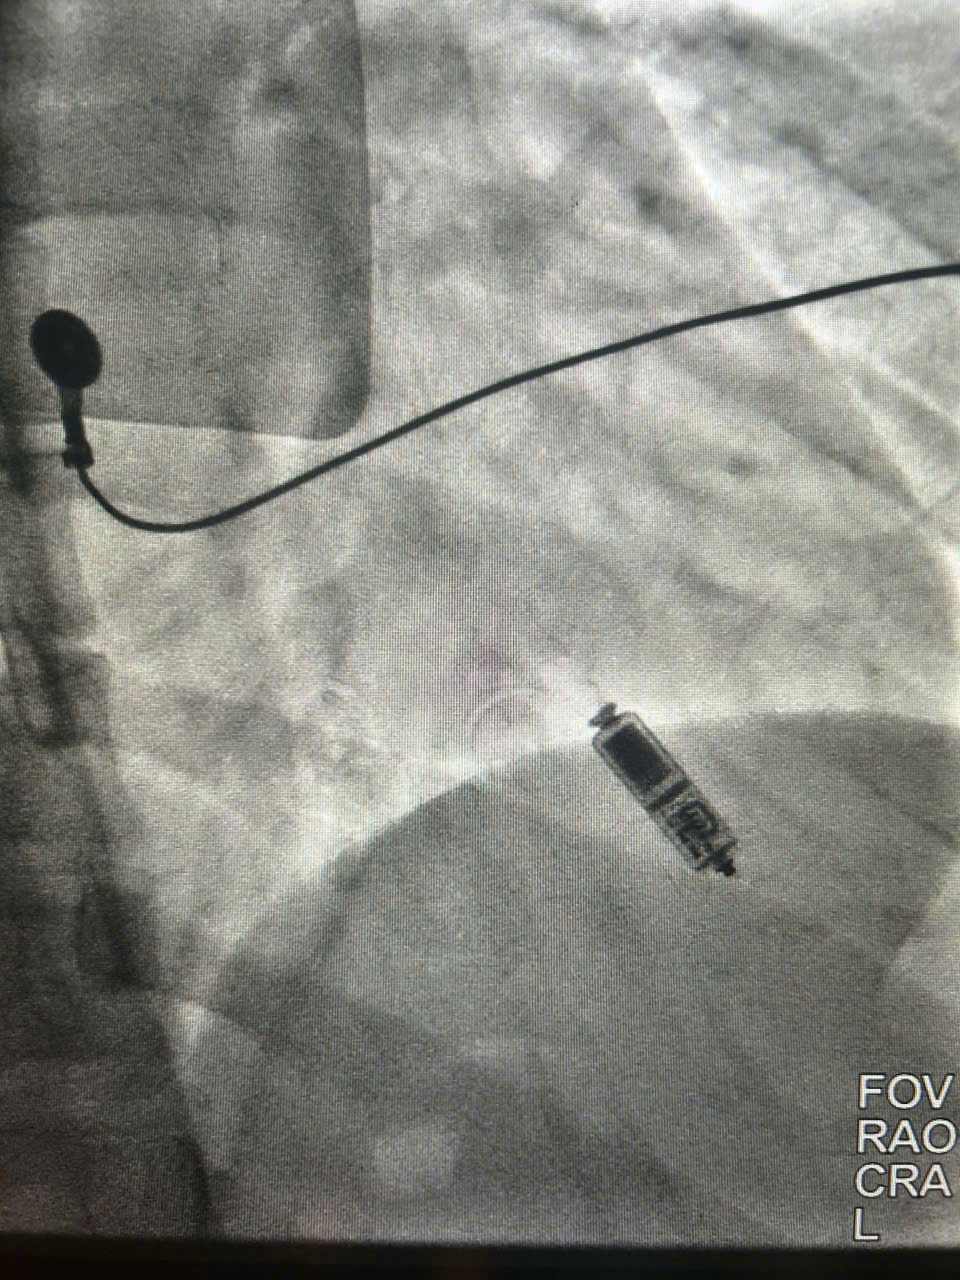

Thiết bị tạo nhịp không dây được cấy trong lồng ngực bệnh nhân

Theo Đại tá PGS, TS Phạm Trường Sơn – Viện trưởng Viện Tim mạch, Chủ nhiệm Khoa Nội tim mạch chia sẻ “Trong nhiều thập kỷ, máy tạo nhịp tim có dây là "tiêu chuẩn vàng" để cứu sống bệnh nhân mắc nhịp chậm. Tuy nhiên, hệ thống này vẫn tồn tại những điểm yếu do cấu tạo phức tạp như: biến chứng tại ổ máy, dây điện cực luồn qua tĩnh mạch vào tim có thể bị đứt gãy, gây huyết khối hoặc nhiễm trùng nội tâm mạc theo thời gian, khiến việc xử lý sau đó cực kỳ phức tạp. Trong nhiều trường hợp phải Hubet8888 lì xì hội viên mới lấy toàn bộ hệ thống ra, vết sẹo và gờ máy nổi lên dưới da thường gây tâm lý tự ti cho bệnh nhân, đặc biệt là phụ nữ và những người trẻ tuổi. Với phương pháp can thiệp bằng thiết bị tạo nhịp không dây là giải pháp đột phá. Thiết bị này chỉ nhỏ bằng thỏi bút chì (nhỏ hơn 90% so với máy truyền thống), được đưa trực tiếp vào buồng tâm thất phải thông qua ống thông đường tĩnh mạch đùi nhằm triệt tiêu nguy cơ biến chứng liên quan đến điện cực, không rạch da vùng ngực, không tạo túi máy, giúp rút ngắn thời gian hồi phục và tối ưu hóa yếu tố thẩm mỹ, giảm thiểu nhiễm trùng.

Máy tạo nhịp không dây chỉ nhỏ bằng thỏi bút chì